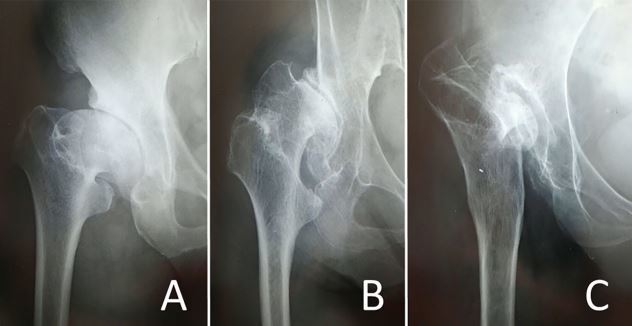

图2:A为 CroweⅠ,小的ATD ;B为CroweⅢ,正常ATD; C为 CroweⅣ,负的ATD。